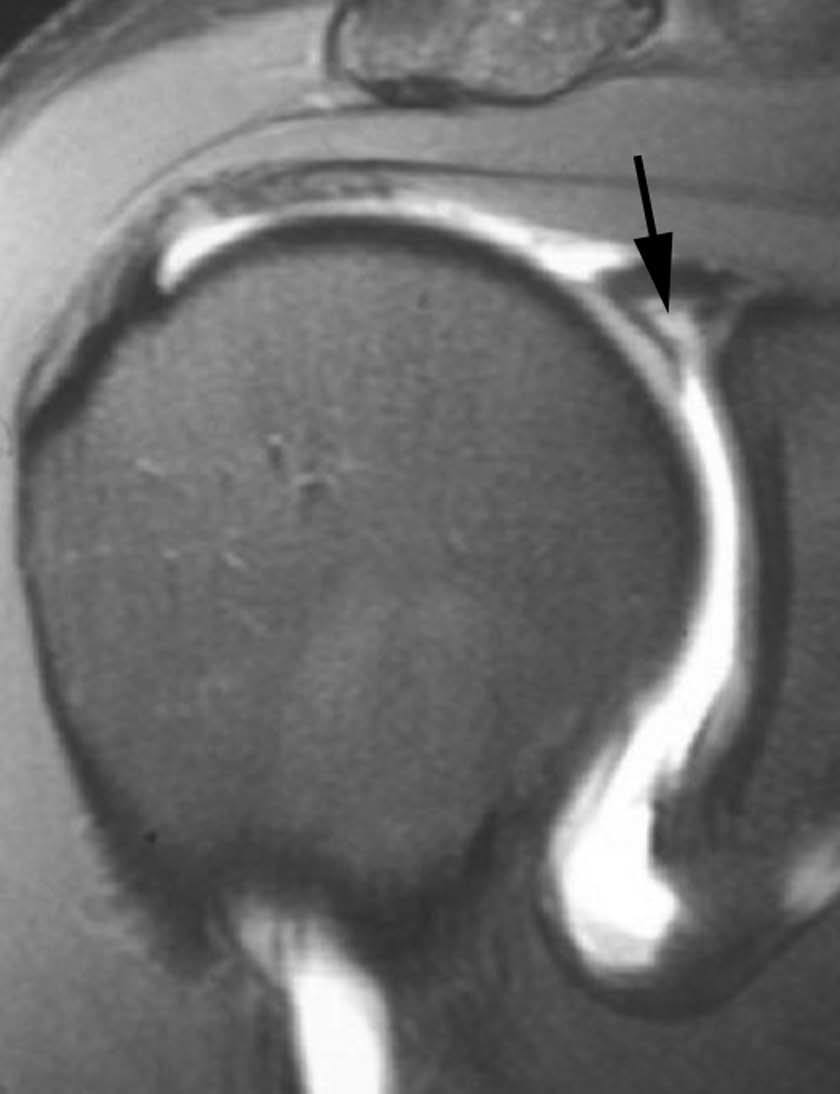

Esta lesión se produce a consecuencia de una tracción repetitiva de la unión cápsulo-perióstica posterior, produciéndose una osificación semejante a un espolón óseo (fig. 15).

Fig. 15.--Lesión de Bennett. Tomografía axial computarizada (TAC) axial (A) y resonancia magnética (RM) T1 axial (B) que revelan la presencia de un «espolón» óseo adyacente al borde glenoideo posterior (flechas en A y B). Nótese la ausencia de una lesión del labio glenoideo posterior en B.